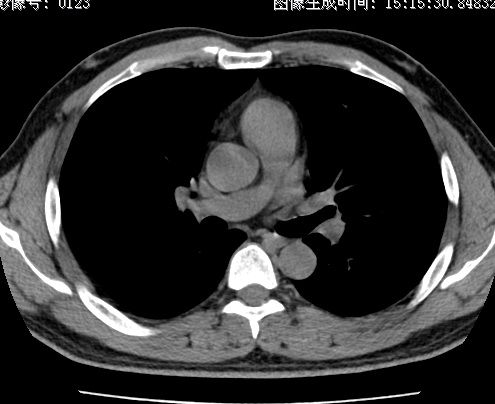

以下是引用zhao_bin2008在2010-1-4 20:15:00的发言:[br]先天性肺囊肿或小的肺隔离症?

以下是引用卜一在2010-1-4 22:09:00的发言:[br]先天性肺囊肿或小的肺隔离症?支持!

以下是引用zsl6918在2010-1-5 5:23:00的发言:[br]良性改变!肺囊肿,先天性支气管闭锁,血管畸形等均有可能。

以下是引用影像之路在2010-1-6 11:10:00的发言:[br]腺癌,最终的病检有些出乎意料之外,术前同志们大多考虑为肺囊肿或小的肺隔离征 [br]回过头来看 小结节呈分叶状,其内侧有一条较粗的静脉供血或许能成为支持诊断腺癌的理由